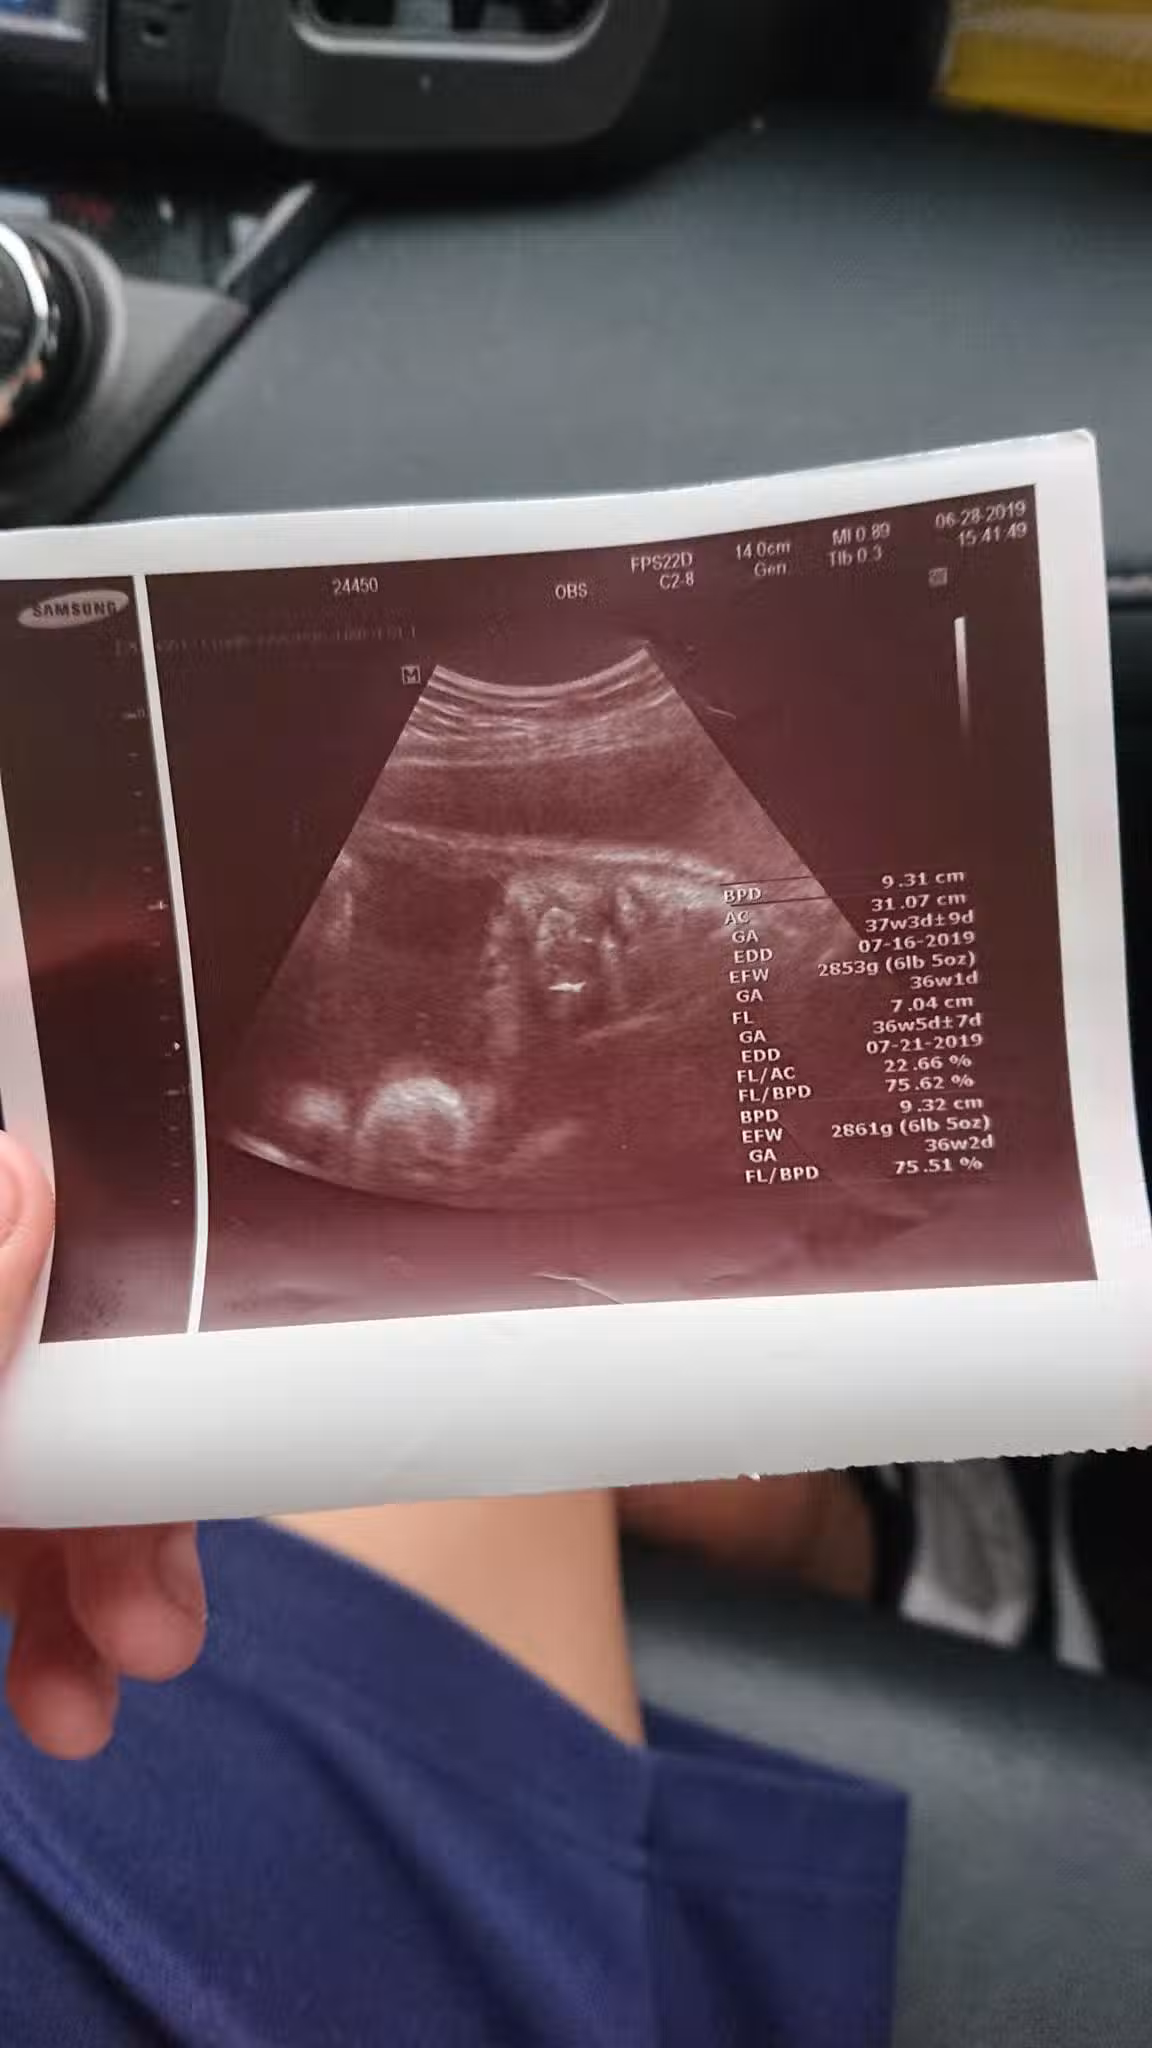

圖片來源:爆怨公社

沒想到兒子女友已經懷孕7個月了,當下他只覺得完蛋了,不知女方家長會怎麼處理,就先帶著高一兒子去見女方家長,還好女方家長很明理,認為事情發生了罵也沒用,就好好讓事情圓滿落幕,由於女方一直不敢告訴家人,所以也沒做產檢,去醫院檢查後,醫生說「胎兒是個男孩,已經約37週大,而且預產期大約在7月中」,所以孩子是一定要生下來的,當時7月1號時女方再度去醫院,竟然已經開了2指,然後7月2號早上小孩就出生了,原PO看到小孫子很開心也很激動,還自嘲說「在我42歲這年,我當上了阿公,我老婆38歲當了阿嬤,而我兒子竟然只給我們4天的時間心理準備……太刺激的禮物了。」。